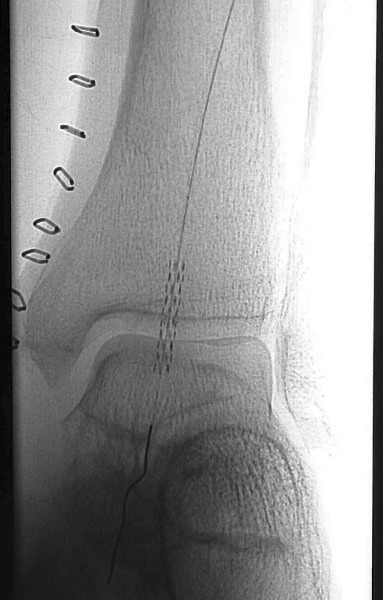

After completing angiogram procedures, surgeons performed an antegrade puncture of the left common femoral artery and placed a 6-Fr sidearm sheath with its tip in the proximal superficial femoral artery. A repeat diagnostic study confirmed the previous findings. The team subsequently used a 4-Fr Berenstein catheter with glide coating (Boston Scientific) loaded with a .014-inch guidewire (Sparta/Core 14, Guidant Corp.) to catheterize the anterior tibial artery and cross the stenosis. The vascular surgeons performed cryoplasty therapy with a 3 mm by 20 mm PolarCath Peripheral System balloon (CryoVascular Systems, Inc.). A post-op control angiogram showed excellent results with a less than 10 percent residual stenosis and no angiographic evidence of dissection. The vascular surgeons proceeded to turn their attention toward the occluded segment of the anterior tibial artery. They advanced the 4-Fr glide Berenstein catheter across the aforementioned treated segment and placed the tip of the catheter just above the occluded portion of the artery. After injecting contrast, the surgeons documented reconstitution of the post-obstructed anterior tibial artery. The surgical team crossed the obstructed segment with a 0.035-inch straight, stiff Glidewire (Boston Scientific), advanced the catheter across the obstruction and confirmed its intraluminal position with a contrast injection. Using the 3.0 mm balloon, they treated the obstructed segment with cryoplasty therapy. A post-op control angiogram disclosed minimal residual stenosis and no vessel wall dissection. There was no evidence of distal embolization of plaque fragments. The vascular surgeons advanced the 0.014 inch guidewire through the balloon catheter and crossed the stenosis of the dorsalis pedis artery again, utilizing a roadmap technique. They treated the stenosis of the dorsalis pedis artery at and below the ankle with a 2.5 mm by 20 mm CryoPlasty balloon. A post-op control angiogram showed significant improvement in the diameter of the dorsalis pedis artery with a focal area of spasm at its mid-portion. The patient tolerated the procedure well and the multidisciplinary team noted a strong, palpable dorsalis pedis pulse after the procedure.